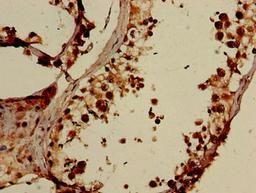

- Immunohistochemistry (IHC)